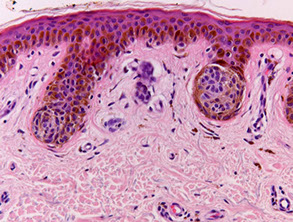

Trichilemmoma

Small, solitary asx papular lesion seen almost always on the face

- arises from trichilemmal part of follicle (c clear glycogenated cells)

Micro: differentiate toward outer root sheath

- sharply circumscribed, c lobules extending to upper dermis and in continuity with the epidermis or follicular epithelium

Some think is a form of a wart involving a hair follicle, or maybe a b9 follicular tumor

Basically is warty surface with hair follicle bottom

Look like the glycogenated outer root sheath of normal hair follicle

- can form cutaneous horns, which can also be seen in warts, SCC, actinic keratosis

- assoc c Cowden syndrome (PTEN gene) if multiple, aka PTEN hamartoma tumor syndrome (visceral hamartomas, thyroid adenomas, ovarian cysts, subcutaneous lipomas and neuromas, GI polyps, carcinomas of the breast and thyroid)

Pale lobules made of clear glycogenated cells (glycogen washed  during processing) attached to epidermis c peripheral palisading and outlined by thick glassy red "vitreous" BM

DDx: SCC (must have atypia to dx SCC)

Trichilemmoma forming a cutaneous horn bottom part is large and pushing into dermis

Trichilemmoma - Papillomatosis with overlying parakeratosis and some     orthokeratosis (without nuclei); also seen in warts

Trichilemmoma - blood and serum in the keratosis (can also be seen in warts)

Trichilemmoma - base of lesion has palisading outside layer of cells next to clear glycogenated cells, like a hair follicle